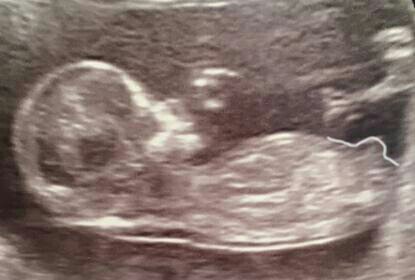

Attachment 30741http://uploads.tapatalk-cdn.com/2016...5c590ca216.jpg

I've outlined the nub for you. The angle of it is pointing straight up, which is very boyish.